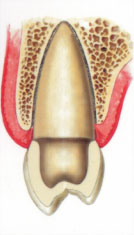

Зубной имплантат - небольшой "искусственный корень", вживляемый взамен утраченного. Имплантат срастается с костью и становится твердой опорой для ваших новых зубов. Если у Вас отсутствует один или несколько зубов, вам не придется обтачивать зубы для установки зубного протеза, если можно установить имплантат, В результате потери зубов на кость уменьшается нагрузка - это приводит к ее атрофии, и смещению зубов в строну дефекта. Со временем появляются морщины вокруг рта, меняется контур лица.

Имплантат будет оказывать нагрузку на кость при жевании, а коронки на имплантате будут поддерживать губы и щеки, помогут вам выглядеть достойно и сохранят форму вашему лицу. Преимушества имплантации 1. Установив имплантат, не придется обтачивать зубы для установки зубного протеза! 2. Имплантат можно установить вместо удаленного зуба в течение одного дня вместе с временной коронкой! 3. Установив имплантат, Ваш съемный протез станет несъемным! 4. Имплантат удержит съемный протез во рту, чтоб протез не выскочил изо рта в самый неподходящий момент. 5. Протезируясь металлокерамическими протезами на имплантате, вкусовые ощущения пищи не изменятся в отличие от съемных протезов которые могут искажать вкус пищи. 6. Установив металлокерамическую коронку на имплантат, улучшается эстетика: уменьшаются морщины вокруг рта, лицо и улыбка молодеет. 7. Установив имплантат улучшается эстетика – коронка на имплантате выглядит так же, как собственный зуб. 8. Установив металлокерамическую коронку на имплантат, Вы восстанавливаете жевательную эффективность на 90%. 9. Уменьшается атрофия альвеолярного гребня кости, восстанавливается нагрузка на кость. 10. После протезирования на имплантате ваше пищеварение будет улучшено, так как пища будет лучше разжевываться и измельчаться, это нормализует работу желудочно-кишечного тракта.